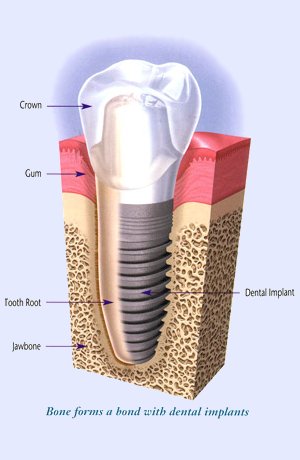

Zubni implanti ili implantati su cilindrični šrafovi koji se ugrađuju u kost vilice i koriste se kao zamena za prirodni koren zuba. Izrađuju se od titanijuma. Zajedno sa nadgradnjom i protetskom krunom zuba čine jedinstvenu celinu za funkcionalnu i estetsku rehabilitaciju jednog ili više zuba koji nedostaju. Kod same ugradnje implanta cilj je ostvariti kontakt spoljašnje površine implanta i okolnog koštanog tkiva kako bi srasli zajedno (pojava se naziva “osteointegracija“) i tako osigurali trajnost zubne nadoknade.

- Implantati se hirurški ugrađuju u kost. Postupak je brzo gotov i bezbolan, budući da se izvodi pod lokalnom anestezijom. Nakon ugradnje implant srasta sa kosti - “osteointegracija“ , što obično traje 2 do 6 meseci.

- Nakon ovog perioda na implant se postavlja nadgradnja (suprastruktura) na koju ide protetska krunica ili neko drugo protetsko resenje u zavisnosti od plana terapija.